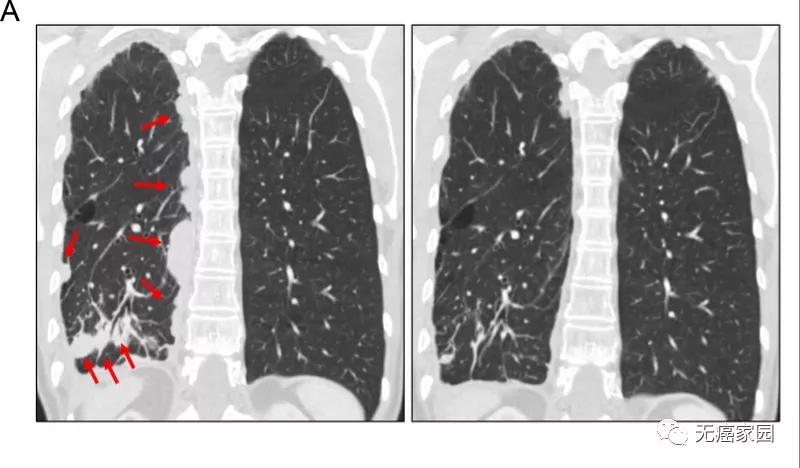

病情开始发生惊人逆转,奥希替尼+BLU-667的用药方案治疗几天后,患者的呼吸困难就显著改善了,8周后影像学可见肿瘤缩小了78%。在治疗16周后进行的随访成像中可以看到确认的部分缓解!

患者1对奥希替尼和 BLU-667 的治疗反应。胸部连续冠状对比增强计算机断层扫描图像显示,在用 BLU-667 和奥希替尼(右)治疗 8 周后,基线(左)看到右下叶肺肿块和胸膜结节(红色箭头),部分反应。